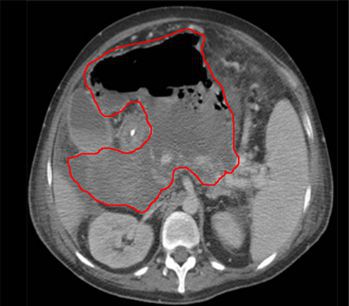

An intra-abdominal abscess is a localized collection of pus in the abdominal cavity. Causes include spontaneous bacterial peritonitis, pelvic infection (e.g. tubo-ovarian abscess), pancreatitis, perforation of the GI tract, and osteomyelitis of the vertebral bodies with extension into the retroperitoneal cavity. It is usually polymicrobial in origin. Diagnosis is made on CT scan or ultrasound. Treatment typically involves antibiotics and drainage of the abscess. The antibiotic regimen should include broad coverage against gram-negative rods, enteroccoci, and anaerobes.